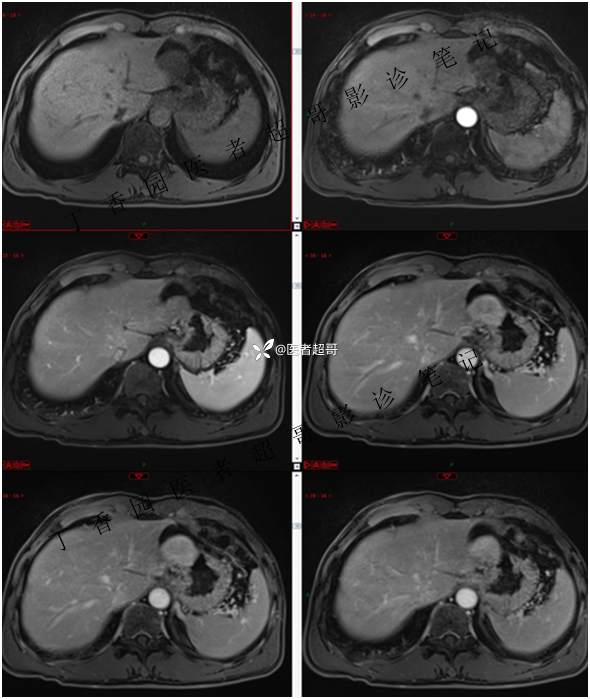

肝胃间隙肿瘤,间质瘤?平滑肌瘤?还是鞘瘤?有结果,请分析!

现病史:患者于3天前查体行肝胆脾胰肾彩超示肝内实性占位,无恶心、呕吐,无发热、寒战,无腹胀、腹泻,进一步于医院行上腹部CT增强示:肝胃交界处肿块。未行特殊治疗。今患者为求进一步治疗,来我院就诊,门诊以“肝占位性病变”收入院。患者自发病以来,神志清,精神可,饮食睡眠可,二便可,体重近期未见明显变化。